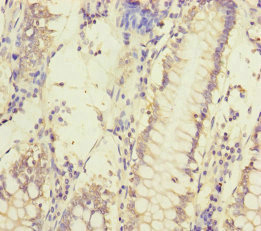

Immunohistochemistry of paraffin-embedded human colon cancer using CSB-PA853497ESR2HU at dilution of 1:100